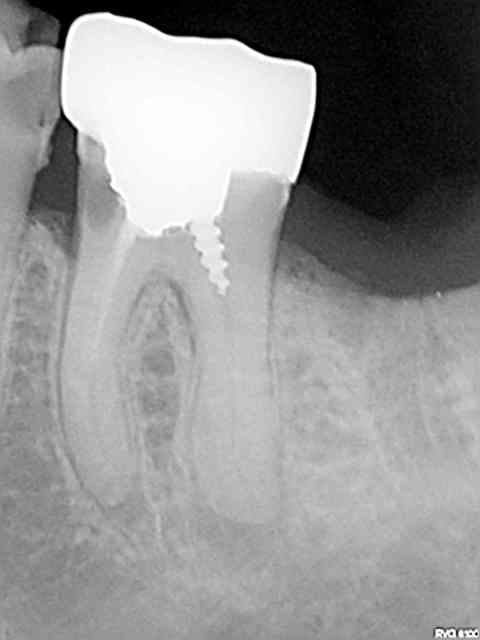

Moi c'est des radios que je vais poster et qu'on ne me dise pas que tous les dentistes se valent. C'est d'ailleurs la meme chose dans toutes les professions, faire croire l'inverse surtout en se basant uniquement sur des prix à la baisse , c'est la merde qui va monter plutôt que la qualité.

Mauvais exemple pour l'endo, c'est le meme prix, grace à qui ? C'est pas un exemple isolé , j'en ai des caisses, mais si je me met à les poster toutes ca va être lourd.